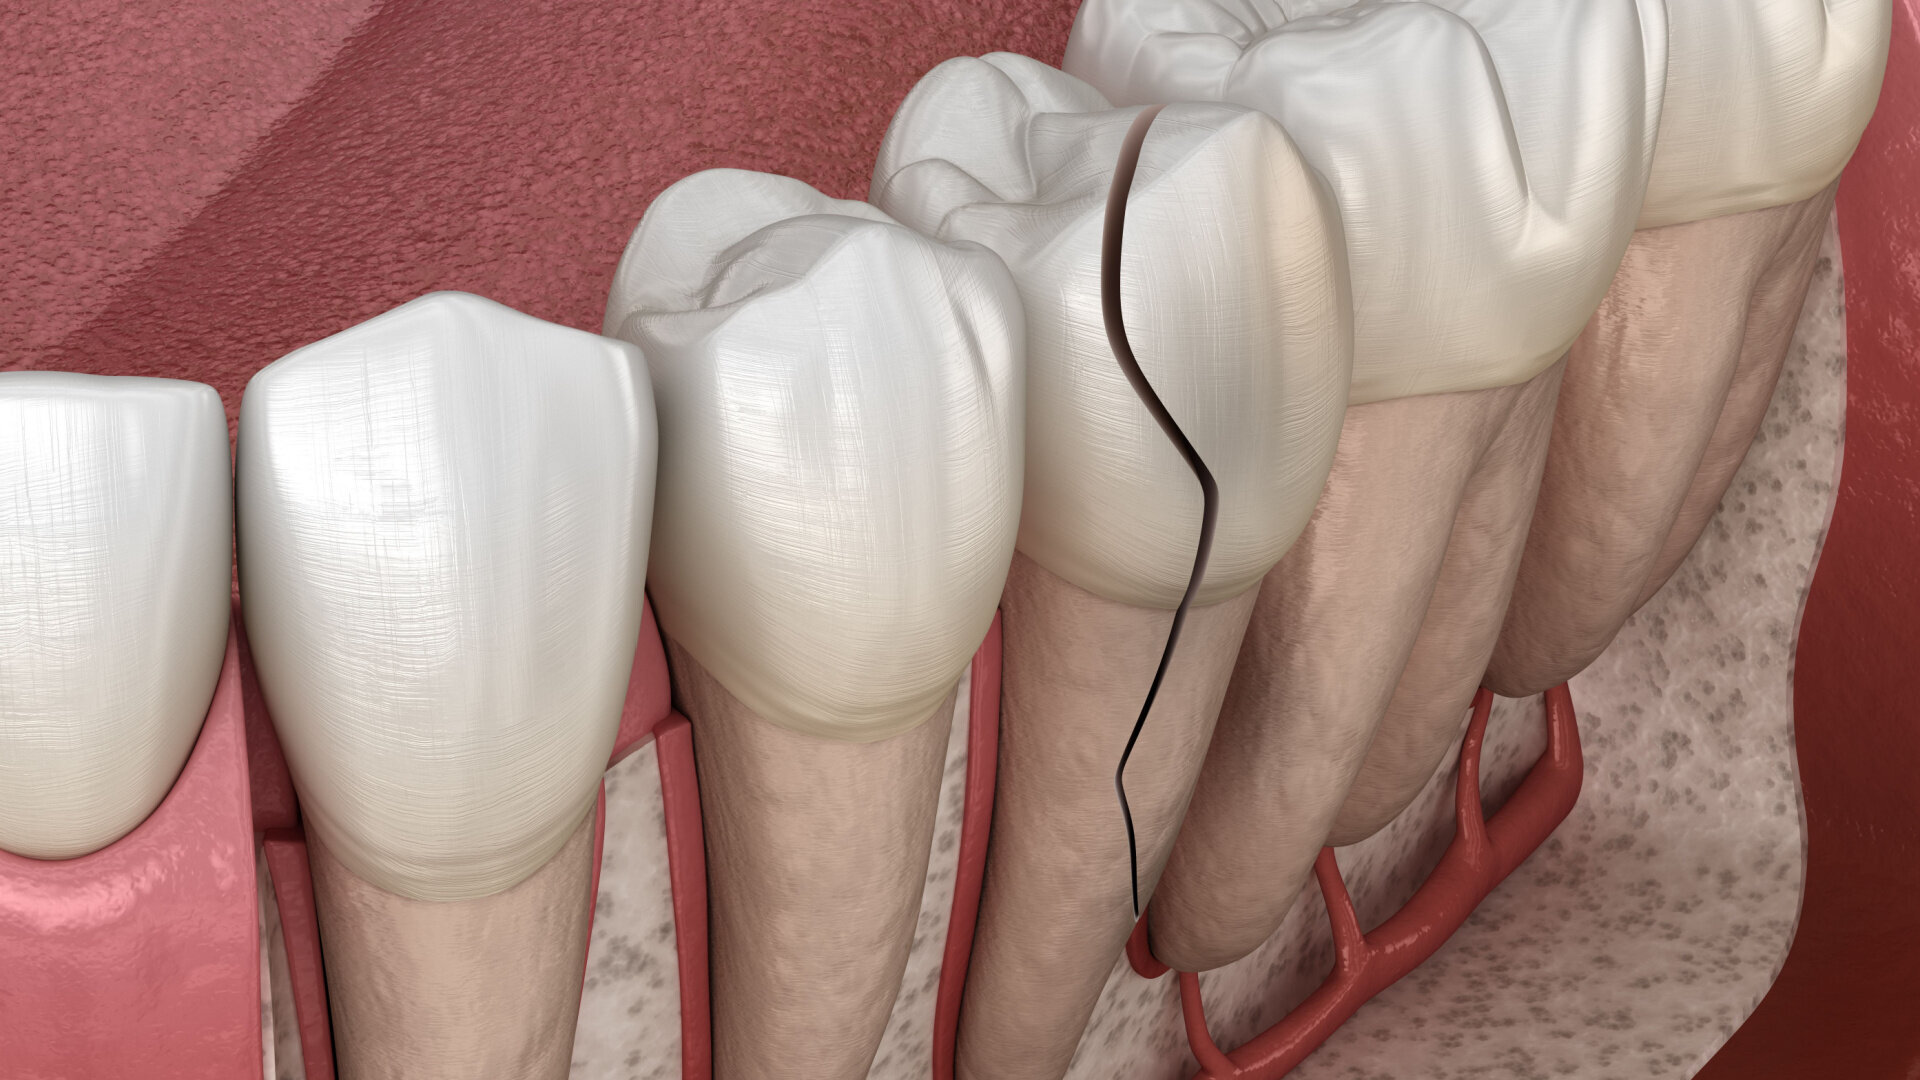

A vertical root fracture (VRF) is a longitudinally oriented fracture of the root that, depending on its cause, can originate from the apex and propagate to the coronal part or the reverse, usually condemning the tooth to extraction. It is more common in endodontically treated teeth, although there are other predisposing risk factors that can trigger cracks that lead to these fractures in vital or necrotic teeth. VRF may develop slowly and without any obvious signs or symptoms, making its diagnosis challenging. Common signs and symptoms are tenderness to percussion, mild pain or dull pain on mastication, gingival swelling, a deep, narrow and isolated periodontal pocket commonly associated with an abscess and the development of a J-shaped radiolucency.1–5

Cracked teeth can lead to a VRF. This is a common clinical scenario in endodontically treated teeth and less common in non-endodontically treated teeth. When a VRF develops, it represents a frustrating scenario, limiting lasting treatment options.15 Multiple treatment strategies have been proposed; however, many of these solutions fail prematurely.16 Retrospective epidemiological studies and case reports do not offer encouraging findings on the long-term treatment outcomes, and there is not a standardised protocol for treating these teeth to date because of the heterogenicity of the clinical situations. Therefore, the prognosis in these cases relies on multiple factors, such as the progression of the fracture line and the damage to the surrounding periodontal structures caused by the infiltration of bacteria and their by-products.15–17

As the majority of VRFs involve loss of periodontal attachment, substantial bone loss is observed as well.17 If a fissure is detected early, a VRF can be avoided, emphasising the importance of a thorough clinical and radiographic examination under the operating microscope and with CBCT imaging.